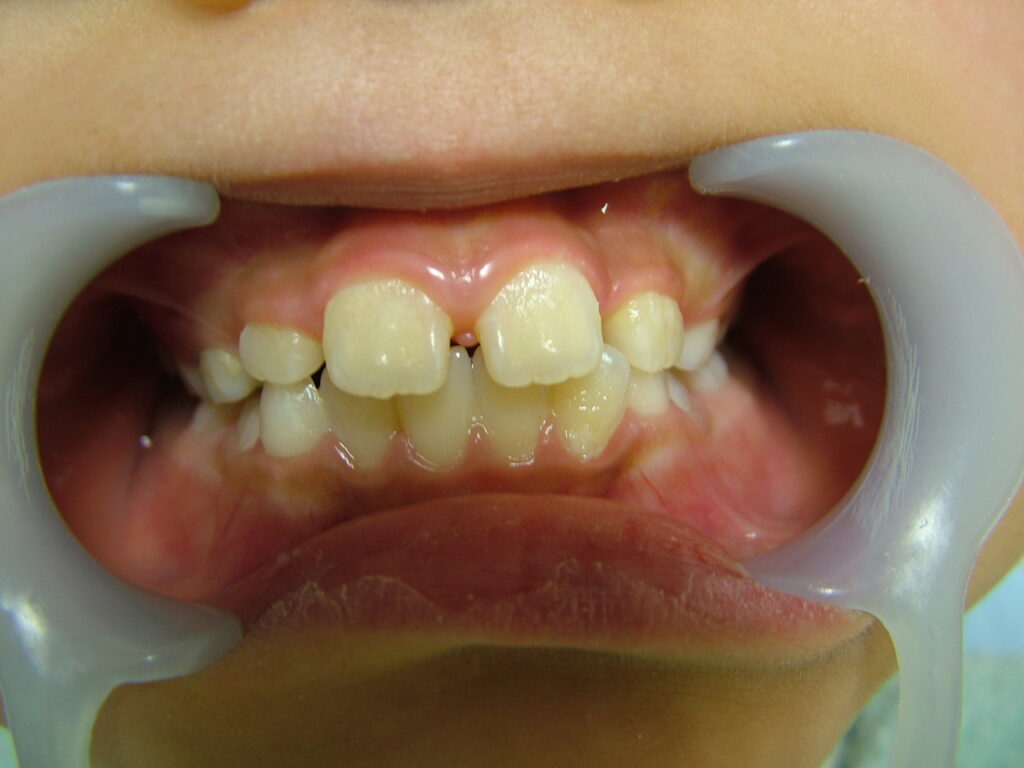

治療前

概要

- 初診:2016年、9歳女児

- 主訴:出っ歯と歯の隙間がきになる。

- 診断:2級過蓋咬合、上下永久歯(犬歯)萌出スペース不足

- 治療方針:非抜歯で行う。虫歯予防(フッ素)、歯磨き指導、上下拡大床→咬合関係改善のツインブロック(2級→1級関係へ)→マウスピース矯正→下親知らずの抜歯、保定→メンテナンス